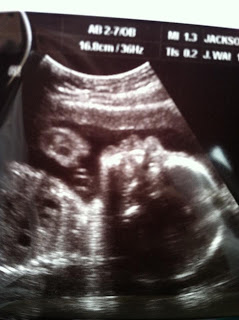

I recently hit the 6 month mark, and everything seemed to be going great with Mr. Bryce. I arrived at my scheduled glucose test last week, and all of the my blood work checked out fine. My belly is also measuring normally. For some reason, my doctor decided to do an exam, and she noticed my cervix felt a bit "short." She told me that she was a little worried and sent me down for an unexpected sonogram. With my luck, Jake was out of town (and I knew he'd be really worried when I called), and it had already been a trying few days. While I felt an all too familiar sensation of anxiety and fear fall over me, I prayed quickly that it would be nothing and that Bryce was doing well. My tech. very sweetly showed me that Bryce is still kicking and looking good, and I was relieved to know he is doing just fine. Thankfully, I measured just above the cut off for bed rest, but my doctor still wants to see me on a two week basis for now. She mentioned bed rest and steroid shots (to help develop Bryce's lungs, etc.) if I begin to have the issues she is concerned about. I am keeping my fingers crossed and praying hard that no such thing happens, and we are able to have him come as expected in mid-January! Many thoughts have gone through my mind, and I have been a bit emotional about the situation (along with several other things); however, God has renewed my strength and given me comfort in knowing he has it all under control. He is good and He is able!! Mrs. Linda has his bedding in the works, and we plan on painting the nursery very soon! I am getting more and more excited at the thought of having another sweet baby in my arms, and knowing I will have a son soon is an amazing feeling!